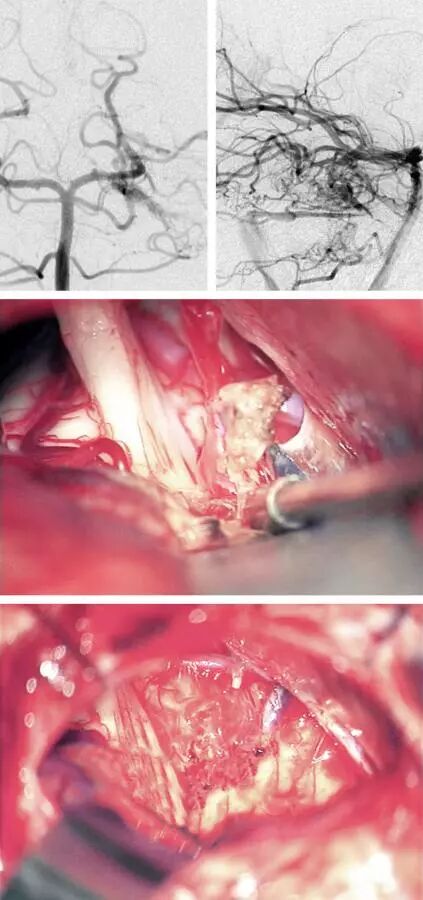

图11:椎动脉造影的前后位与侧位显示一个桥脑外侧的AVM,经岩上窦回流。第二张手术中照片显示岩上窦动脉化的(紫色箭号)与正常的(蓝色箭号)分支,还有畸形巢。三叉神经根出脑干区位于畸形巢的前方。第三张照片显示发自AICA(红色箭号)的供血动脉。切除AVM并离断岩上窦的动脉化部分,岩上窦的正常分支保留完好(蓝色箭号)。手术通路内的SCA无损伤(红色箭号)。

注:Ⅶ/Ⅷ:面神经/听神经。